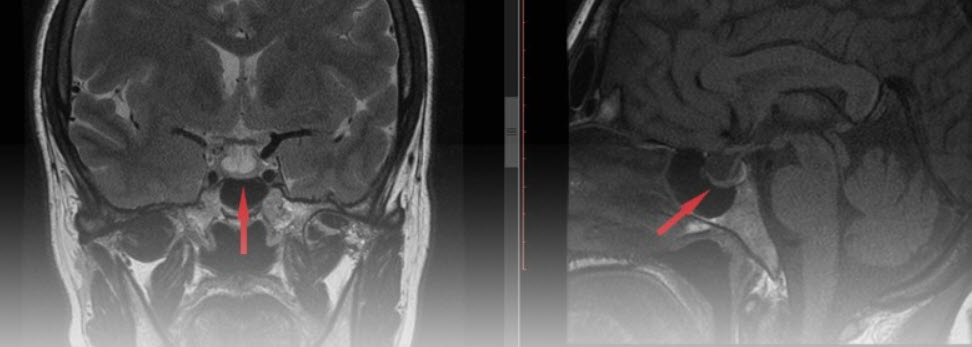

Chẩn đoán hình ảnh: Chụp cộng hưởng từ (MRI) hoặc cắt lớp vi tính (CT) giúp phát hiện u tuyến yên hoặc tổn thương vùng hạ đồi.

Hình ảnh MRI u tuyến yên – nguyên nhân hàng đầu gây suy tuyến yên hiện nay